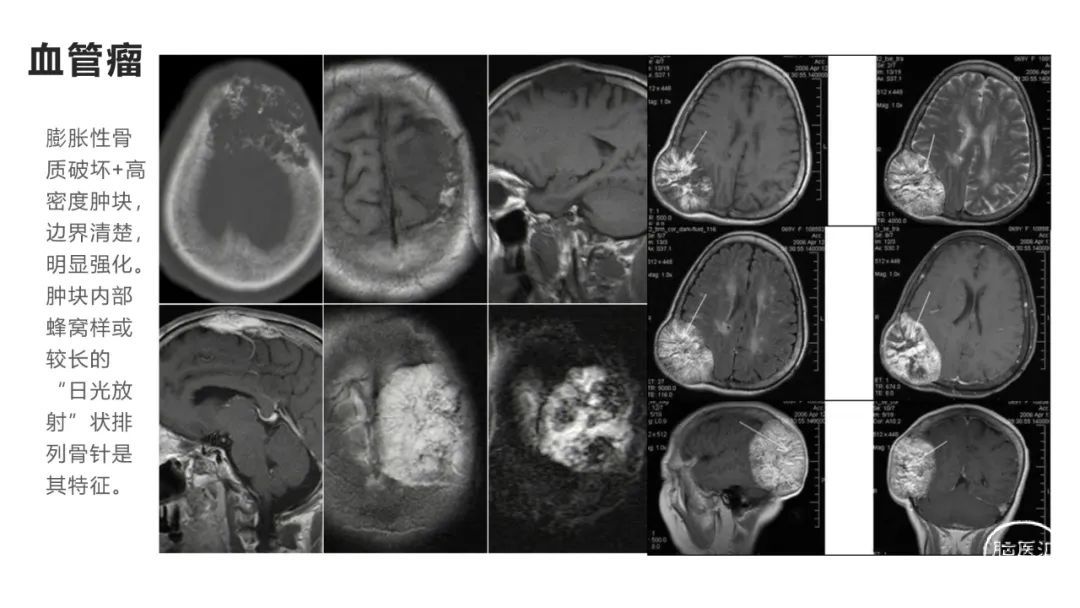

颅脑影像诊断基础知识讲座:颅骨病变